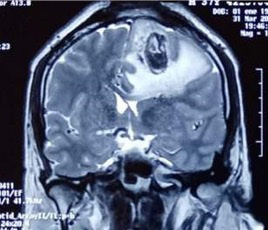

En la tomografía de control se encontraron signos de craniectomía (agujero de trepano) asociada a focos de aire en la región parietal izquierda, edema vasogénico y herniación cerebral parietal izquierda. Por esta razón fue reintervenido quirúrgicamente luego de tres semanas con buena evolución de la lesión (figuras 2 y 3).